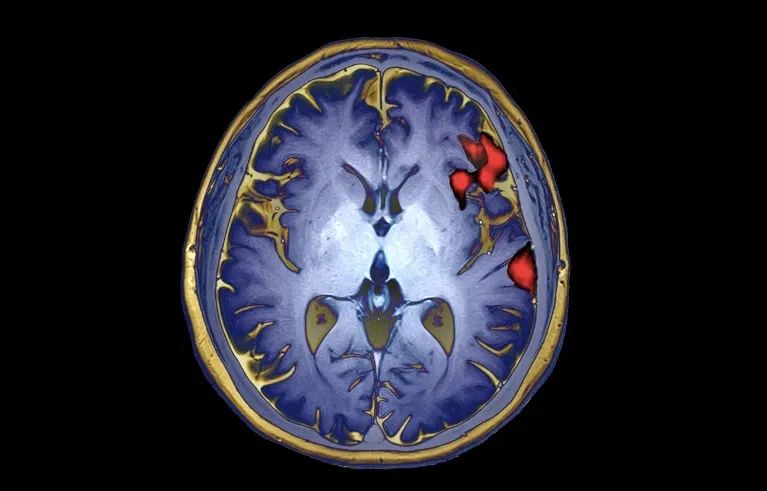

这项研究的参与者,绰号"Pancho(潘乔)",20岁时因中风导致身体大部分瘫痪。因此,他只能发出呻吟和咕哝声,却不能清楚地说话。30多岁时,潘乔与加州大学旧金山分校(University of California, San Francisco)的神经外科医生爱德华·张(Edward Chang)合作,研究中风对他大脑的持久影响。在2012年发表的一项开创性研究中,Chang的团队通过手术将电极植入Pancho的皮层,以记录神经活动,并将其转化为屏幕上的文字。

为了实现这一目标,由Chang的博士生Alexander Silva领导的这项工作开发了一个人工智能系统来破译潘乔的双语语音,包括在Pancho试图说出近200个单词时训练系统。他拼单词的努力创造了一个独特的神经模式,并被电极记录下来。

然后,作者将他们的人工智能系统(包括一个西班牙语模块和一个英语模块)应用于潘乔尝试大声说出的短语。对于短语中的第一个单词,西班牙语模块会选择与神经模式最匹配的西班牙语单词。英语模块也会这样做,但会从英语词汇中进行选择。例如,英语模块可能会选择"she "作为短语中最有可能出现的第一个单词,并评估其正确概率为 70%,而西班牙语模块可能选择“estar”(to be),并评估其正确的概率为40%。

从那里,两个模块试图建立一个短语。他们每个人都选择第二个单词,不仅基于神经模式的匹配,而且还基于它是否可能跟随第一个单词。因此,"I am"会比"I not"获得更高的概率得分。最后输出两个句子——一个用英语,一个用西班牙语——但是Pancho面对的显示屏只显示总概率得分最高的版本。